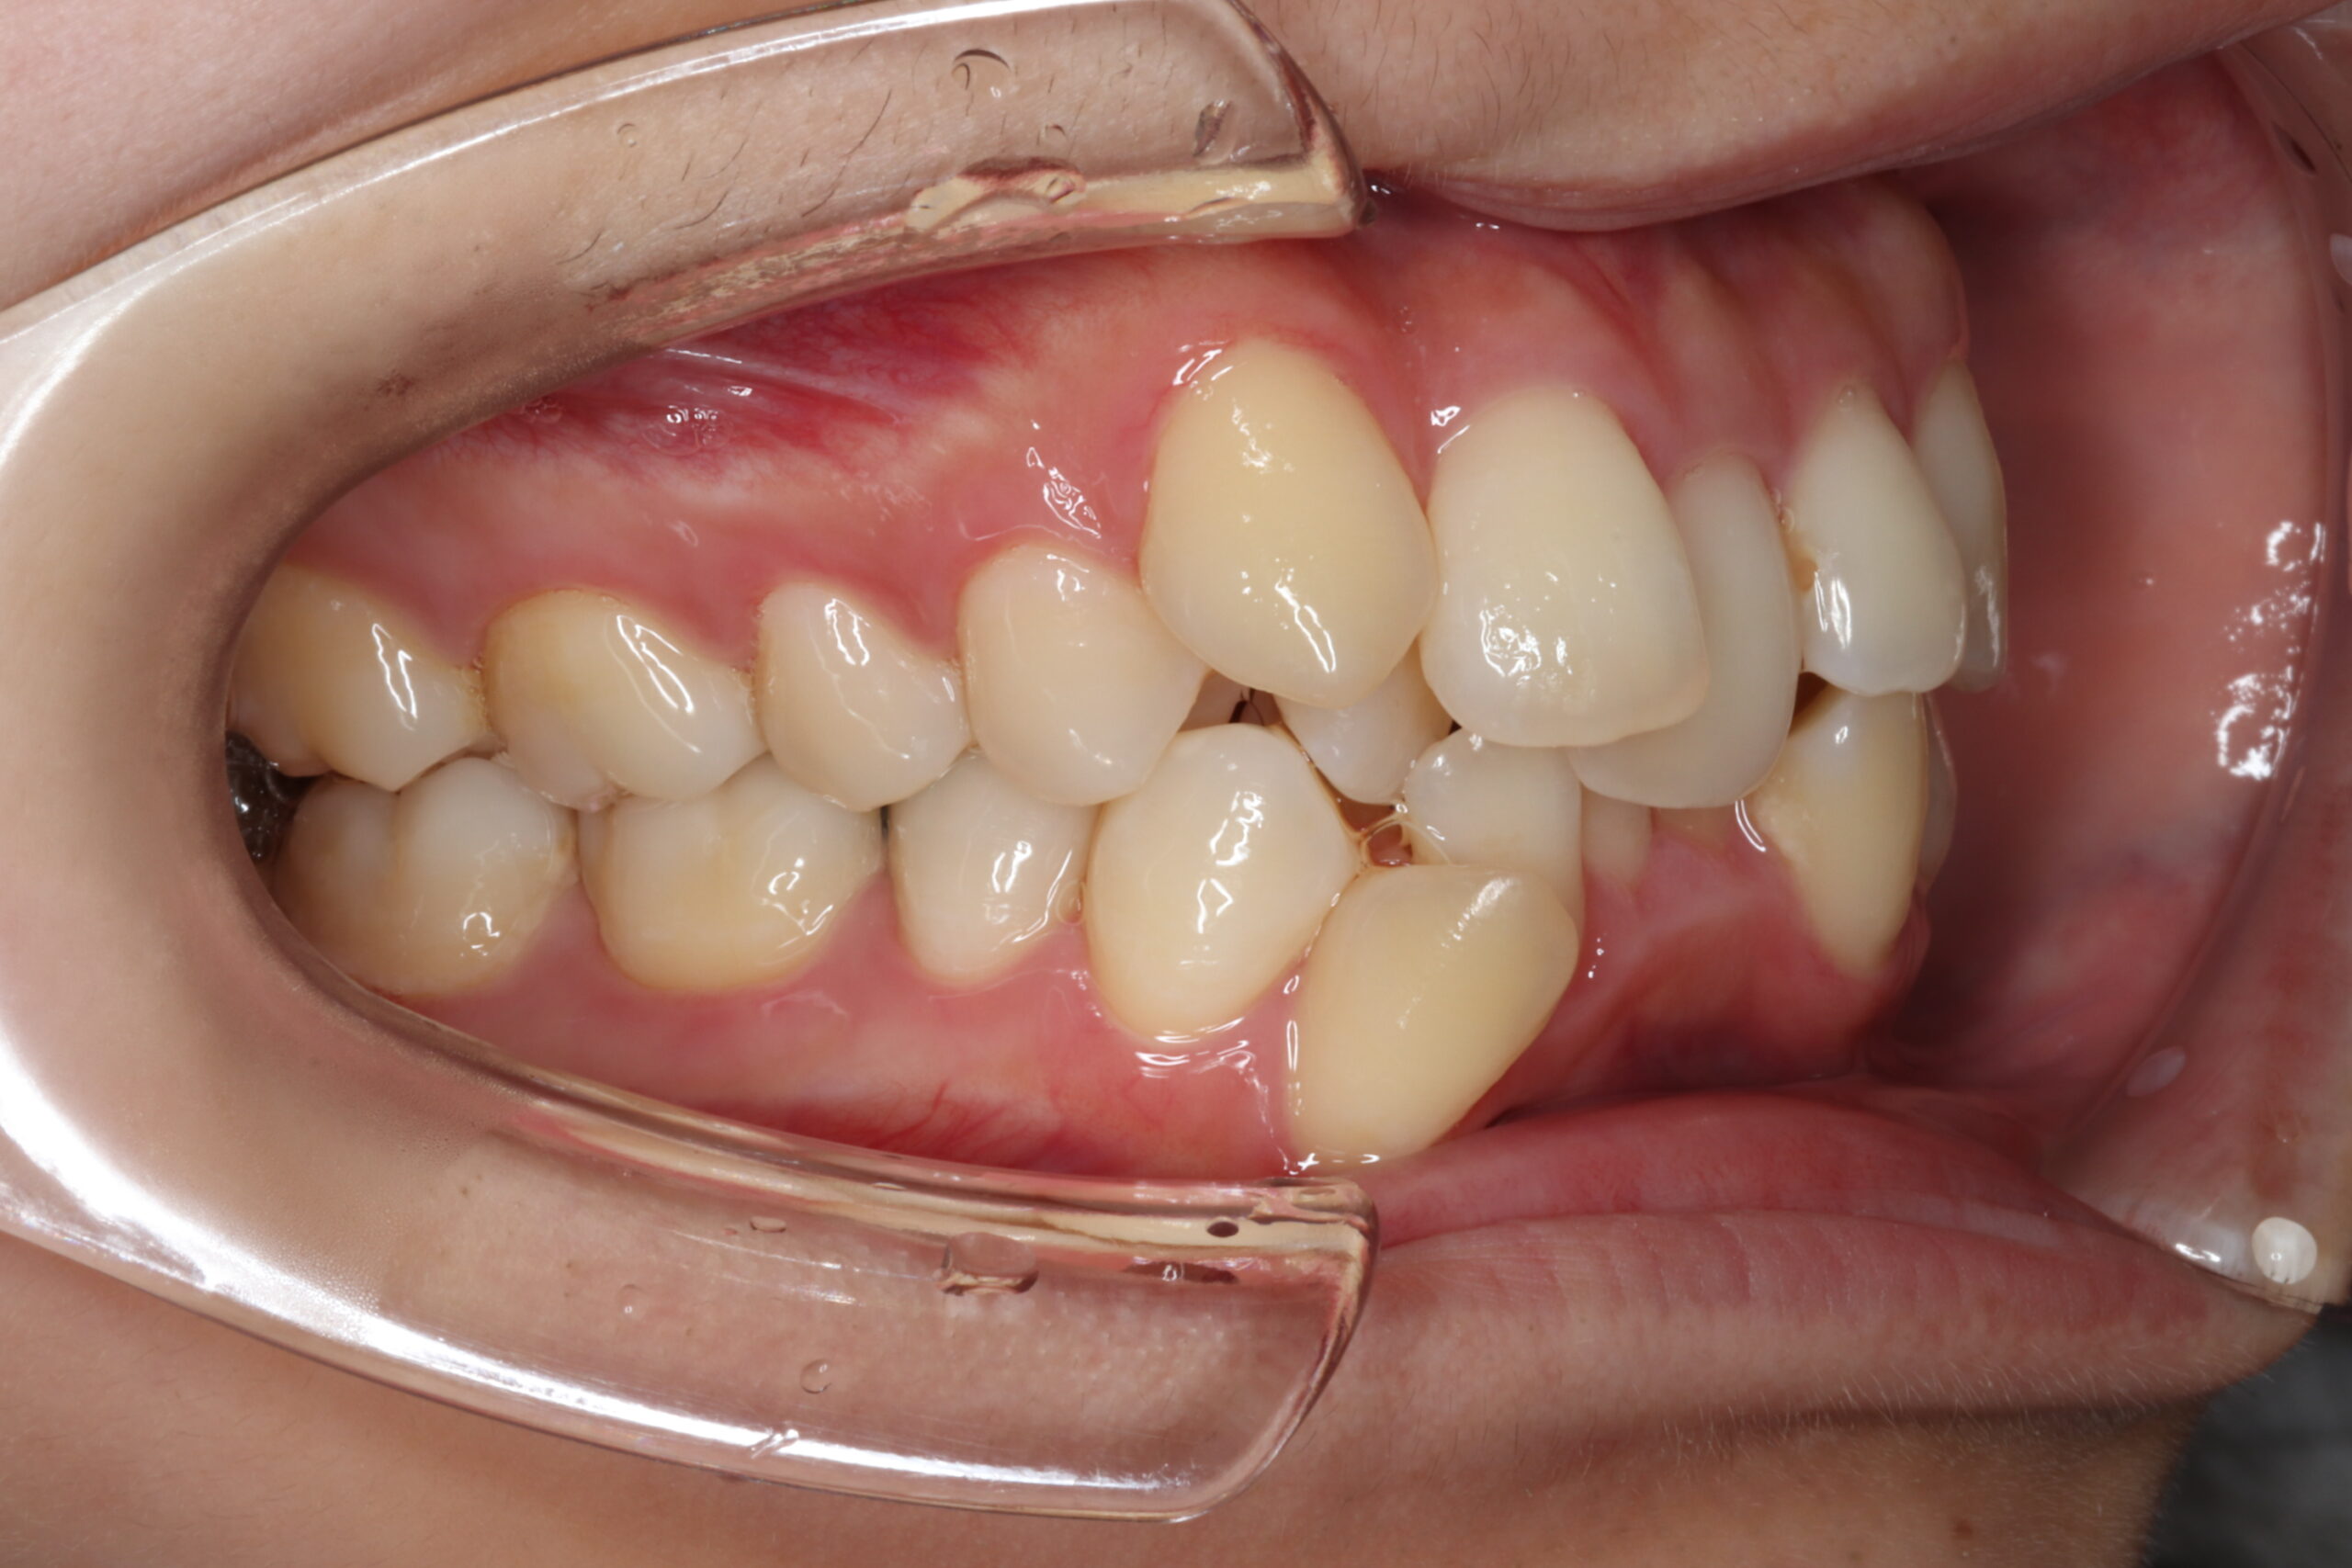

マウスピース矯正やワイヤー矯正に加え、必要に応じてアンカースクリューを活用することで、より複雑で難しい歯並びの症例にも対応しています。これにより、従来の矯正だけでは難しかった歯の移動も可能となり、幅広い治療の選択肢をご提供できます。

症例

矯正歯科専門の歯科医師が専門的な知識と確かな実績を

もとに患者様にあった最適な治療プランをご提案します。